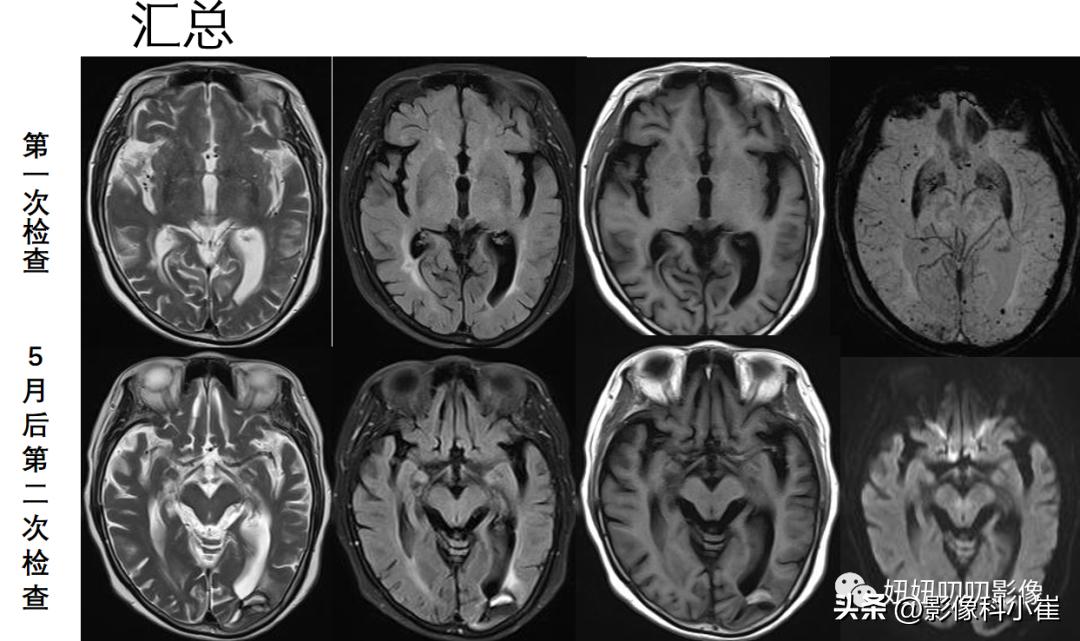

左侧枕叶皮层下见截面大小约 1.6X1.2cm 斑片状短T1、长T2倍号,周围见环状短T2倍号,DWI示病灶弥散受限。耕眠体及双侧大脑半球皮层下、半卵圆中心、侧脑室旁白质、基底节区、丘脑见多发班片状、点状等长 T1 略长 T2 异常信号灶,FLAIR 呈高、低信号,DWI 未见明显弥散受限。脑室系统未见明显扩张,脑沟裂增宽、加深,中线结构未见明显移位。双侧筛窦、上领窦粘膜增厚,呈长T1长T2信号。

SWI:双侧大脑半球表面见多发、弥漫性低信号灶。

第一次的图像,没有SWI打死也想不到脑淀粉样病变;

第二次有脑叶出血了,可以提示做个SWI,然后看到全是微出血灶,所以更提示脑淀粉样血管病了

①:看到SWI能想到,脑淀粉样血管病,出院诊断也是这个;

④:影像:脑叶出血+脑微出血+大脑凸面蛛网膜下腔出血+铁沉积——提示 脑淀粉样血管病;临床:阿尔兹海默病+年龄。